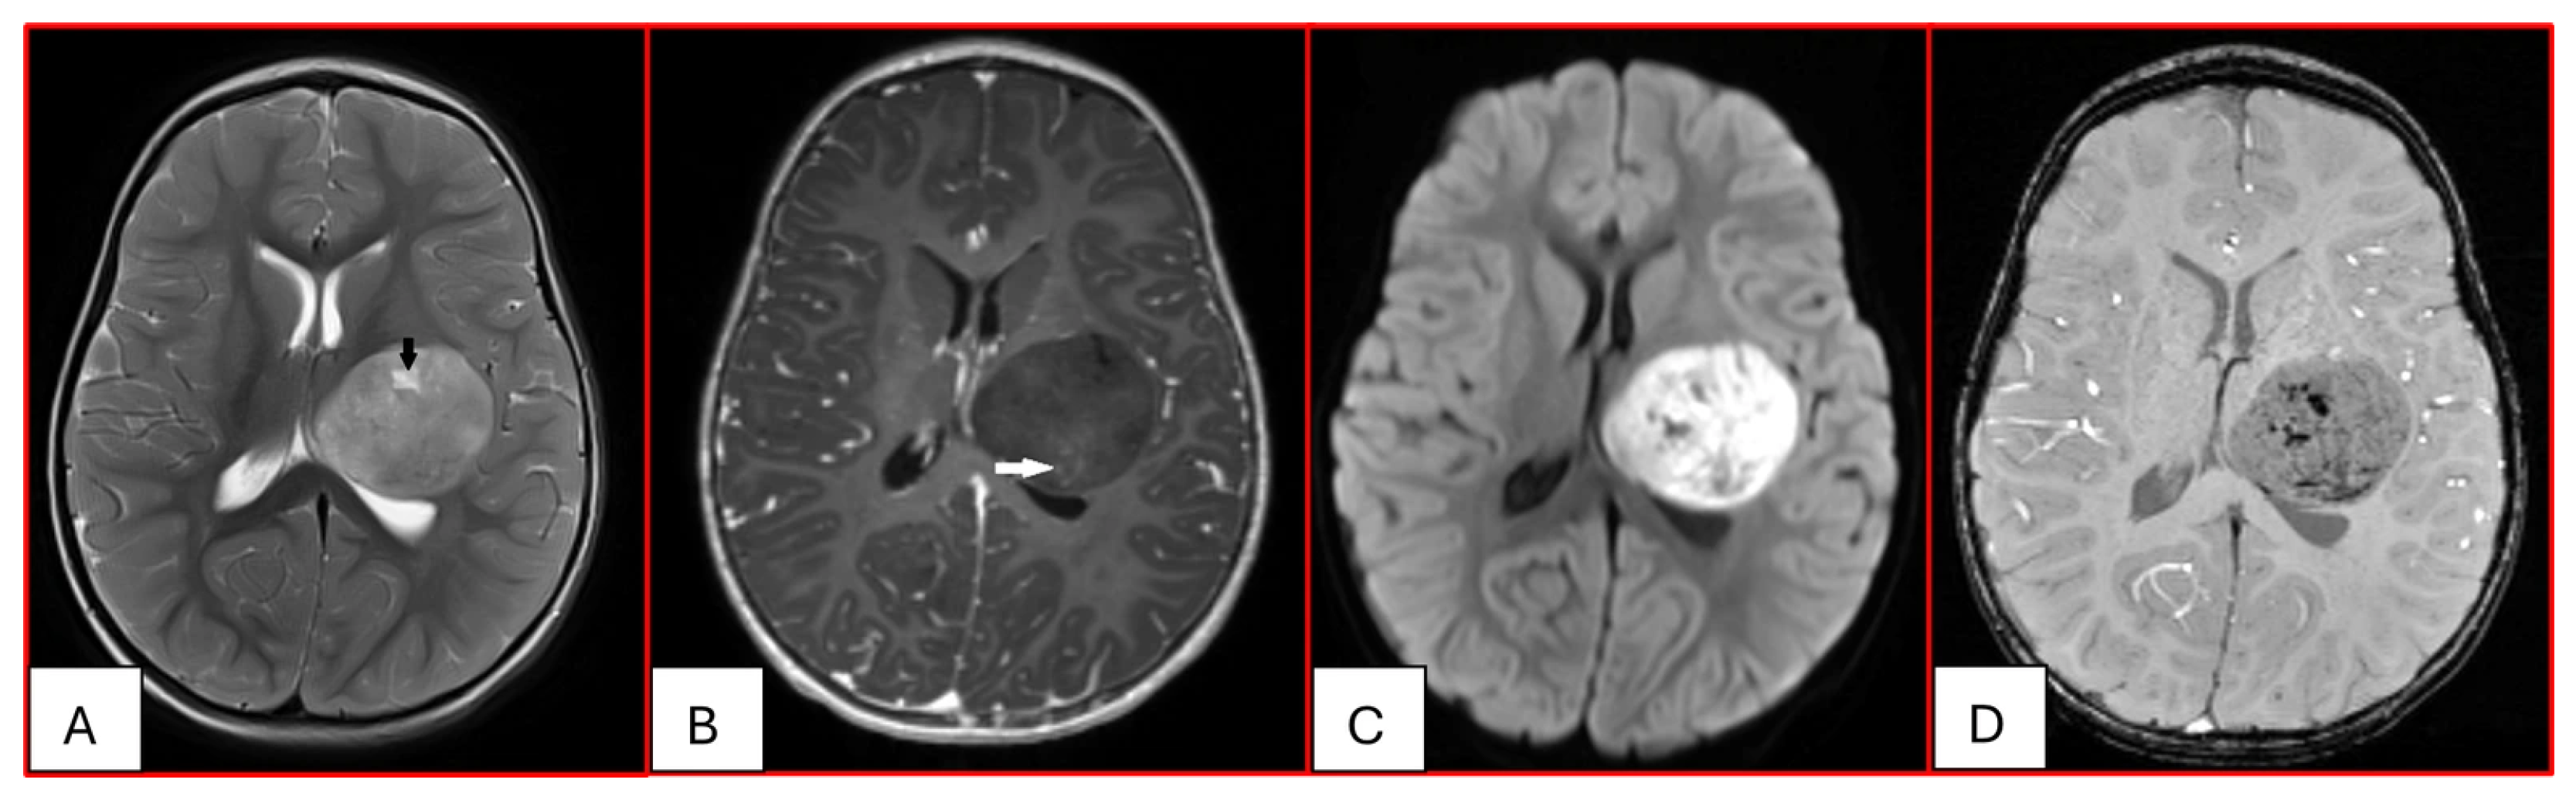

On computed tomography (CT), AT/RTs typically appear hyperdense owing to their high cellularity, and calcifications are frequently identified. Magnetic resonance imaging (MRI) findings are variable on both T1- and T2-weighted sequences; however, restricted diffusion is usually present. Cystic or necrotic components, as well as intratumoral hemorrhage, are common features [15]. Arslanoglu et al. described the presence of eccentrically positioned cysts with peripheral wall enhancement as a potentially distinguishing characteristic of infratentorial AT/RTs (Figure 1). The pattern and degree of contrast enhancement are variable, further reflecting the histopathologic heterogeneity of these neoplasms (Figure 2 and Figure 3). A characteristic pattern of band-like enhancement surrounding a central cystic or necrotic area was observed in 38% of MRIs from a series of 32 patients [16].

Figure 2. Twenty-three-month-old female with ATRT. (A) Axial T2-weighted image reveals a circumscribed supratentorial mass centered in the left deep gray nuclei of heterogeneous intermediate signal with small central cystic/necrotic changes (black arrow). There is no surrounding edema. (B) This mass is predominantly non-enhancing with minimal internal foci of enhancement (white arrow). (C) There is corresponding prominent restricted diffusion. (D) Multiple internal foci of susceptibility are present, which may reflect internal hemorrhage or calcifications.

Figure 3. Three-year-old female with ATRT. (A) Axial T2-weighted image shows a mass centered in the midline posterior fossa of heterogeneous intermediate signal with small cystic/necrotic changes. There is no surrounding edema. (B) This mass demonstrates mild heterogeneous enhancement. (C) There is prominent corresponding restricted diffusion. (D) A few foci of susceptibility are noted, which may reflect internal hemorrhage or calcifications. Note that the MRI features of this mass mimic the appearance of Medulloblastoma.